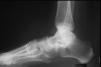

La coalición tarsiana puede ser uni o bilateral, habitualmente única en un pie, pero puede ser también múltiple. Puede ocurrir entre cualquiera de los huesos del tarso, pero la localización más frecuente es la calcaneoescafoidea (aproximadamente el 50% de los casos), seguida de la astragalocalcánea (37%) (fig. 8)3. La barra calcaneoescafoidea es fácilmente identificable en la radiografía en proyección oblicua de la región posterior del tarso, pero no se identifica en las proyecciones de perfil o anteroposterior. La coalición astragalocalcánea es más común en chicos que en chicas, y llega a ser bilateral hasta en la cuarta parte de los casos4. La anquilosis puede asentar en las regiones subastragalinas posterior, media o anterior, pero la más frecuente es la localizada en la región articular media, mientras que la coalición posterior es la más infrecuente. No es fácil de identificar en la radiología simple, pero se observa con facilidad en la tomografía axial computarizada (fig. 9). Se ha descrito una serie de signos radiológicos secundarios, asociados a esta coalición, que facilitan su reconocimiento4, tales como un gancho o pico óseo en la cara superior del astrágalo, adyacente a la articulación astragaloescafoidea (fácilmente evidenciable en la proyección de perfil del pie), pinzamiento de la interlínea articular de la subastragalina posterior y nula visualización de la interlínea articular subastragalina «media». En los casos de coaliciones fibrosas o cartilaginosas el diagnóstico de seguridad se establece con la resonancia magnética nuclear.

Figura 8. Coaliciones tarsianas: calcaneoescafoidea (A) y astragalocalcánea (B).